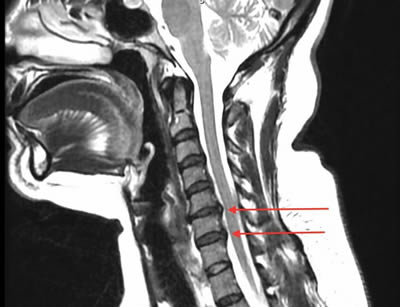

GALLERY

Images gallery